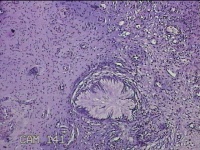

性别

女

年龄

31岁

临床诊断

宫颈上皮内瘤变

一般病史

发现宫颈CIN2 2个月。

标本名称

宫颈组织

大体所见

灰白暗红色组织2.8x1.8x0.3cm一块,表面糜烂,切面灰白暗红色,质软。

所提供图片不具有诊断价值。